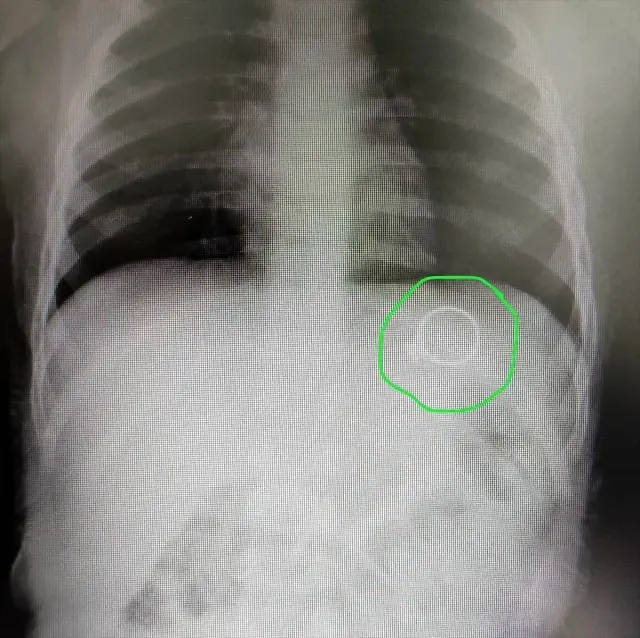

Akciğer filmi iki yönlü olarak çekilir, akciğerler önden ve yandan çekilerek çevre organlarda ve göğüs boşluğunda oluşabilecek hastalıklara da tanı. 8 aylık bebeğime yabancı cisim yutma şüphesiyle röntgen çekildi röntgene baktığımda tüm vücudu çekilmiş zararı ne olur ne kadar etkilendi çok üzğünüm. Ürolitiyazis gibi tehlikeli bir hastalıktan şüpheleniliyorsa, çocuklar önce ultrason taraması için yönlendirilir.bununla birlikte, herhangi bir ultrason.

Anne adayları da bu konuda özenli davranmaları gerekir. Balgamlı öksürüğün asıl nedeninin akciğerlerden kaynaklanmasından dolayı bu aşamada doktor göğüs röntgeni istemektedir. 8 aylık bebeğime yabancı cisim yutma şüphesiyle röntgen çekildi röntgene baktığımda tüm vücudu çekilmiş zararı ne olur ne kadar etkilendi çok üzğünüm.

Akciğer filmi iki yönlü olarak çekilir, akciğerler önden ve yandan çekilerek çevre organlarda ve göğüs boşluğunda oluşabilecek hastalıklara da tanı. 8 aylık bebeğime yabancı cisim yutma şüphesiyle röntgen çekildi röntgene baktığımda tüm vücudu çekilmiş zararı ne olur ne kadar etkilendi çok üzğünüm. Hafta arasında yapılan tek seferlik röntgenler bebekler için herhangi bir sorun yaratmamaktadır.

Sivas'ta annesinin tek taş yüzüğünü yutan 1,5 yaşındaki bebek

Sivas'ta 1,5 yaşındaki bebek, yuttuğu yüzüğü 6 gün sonra